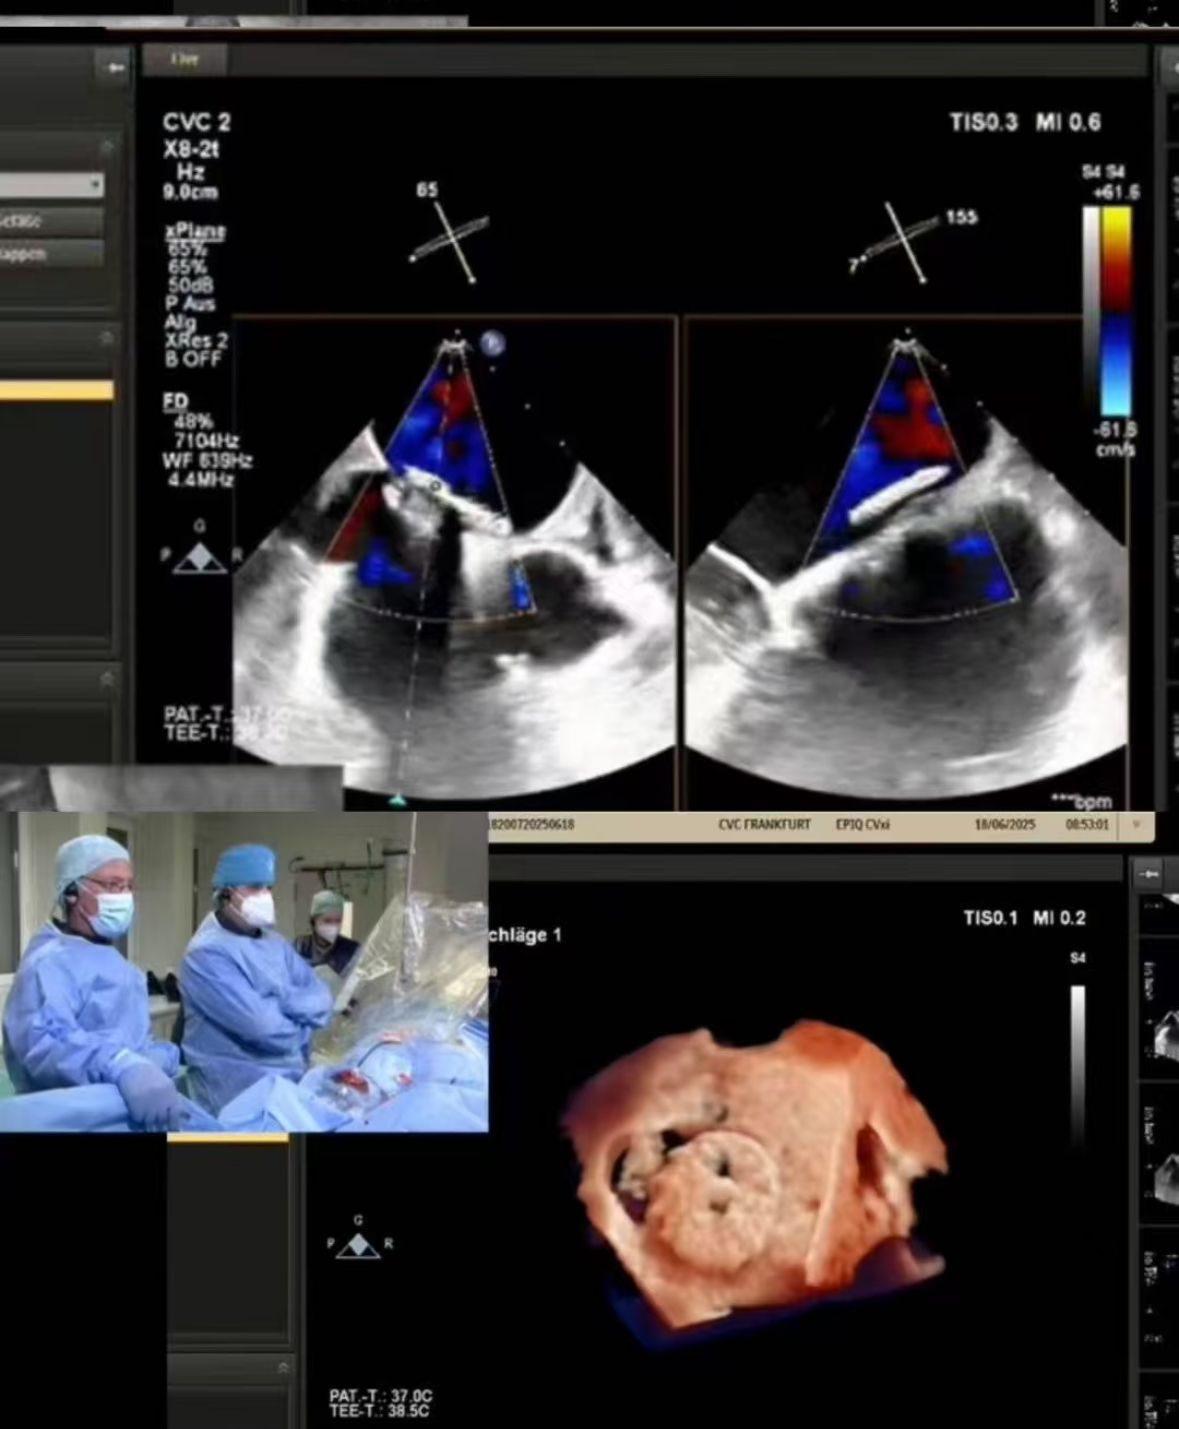

Thrilled to showcase our MemoSorb PFO Occluder – the world's first absorbable device (degrades to water & CO₂ within 1 year) – during a live broadcast from the Blue Room at CSI Frankfurt!

Przesyłaliśmy złożone zamknięcie PFO przeprowadzone w CVC Frankfurt na 60-letniej pacjentce z:

1. Nawracające udary zatorowe (2014, 2021)

2. ciężka alergia na nikiel (przeciwwskazania dla urządzeń metalowych)

3. resztkowy bocznik po uprzednim zamknięciu

2. Precyzyjne zamknięcie: obrazowanie w czasie rzeczywistym sterowane perfekcyjnym wdrożeniem w wymagającej anatomii (fenestracja tunelu PFO).